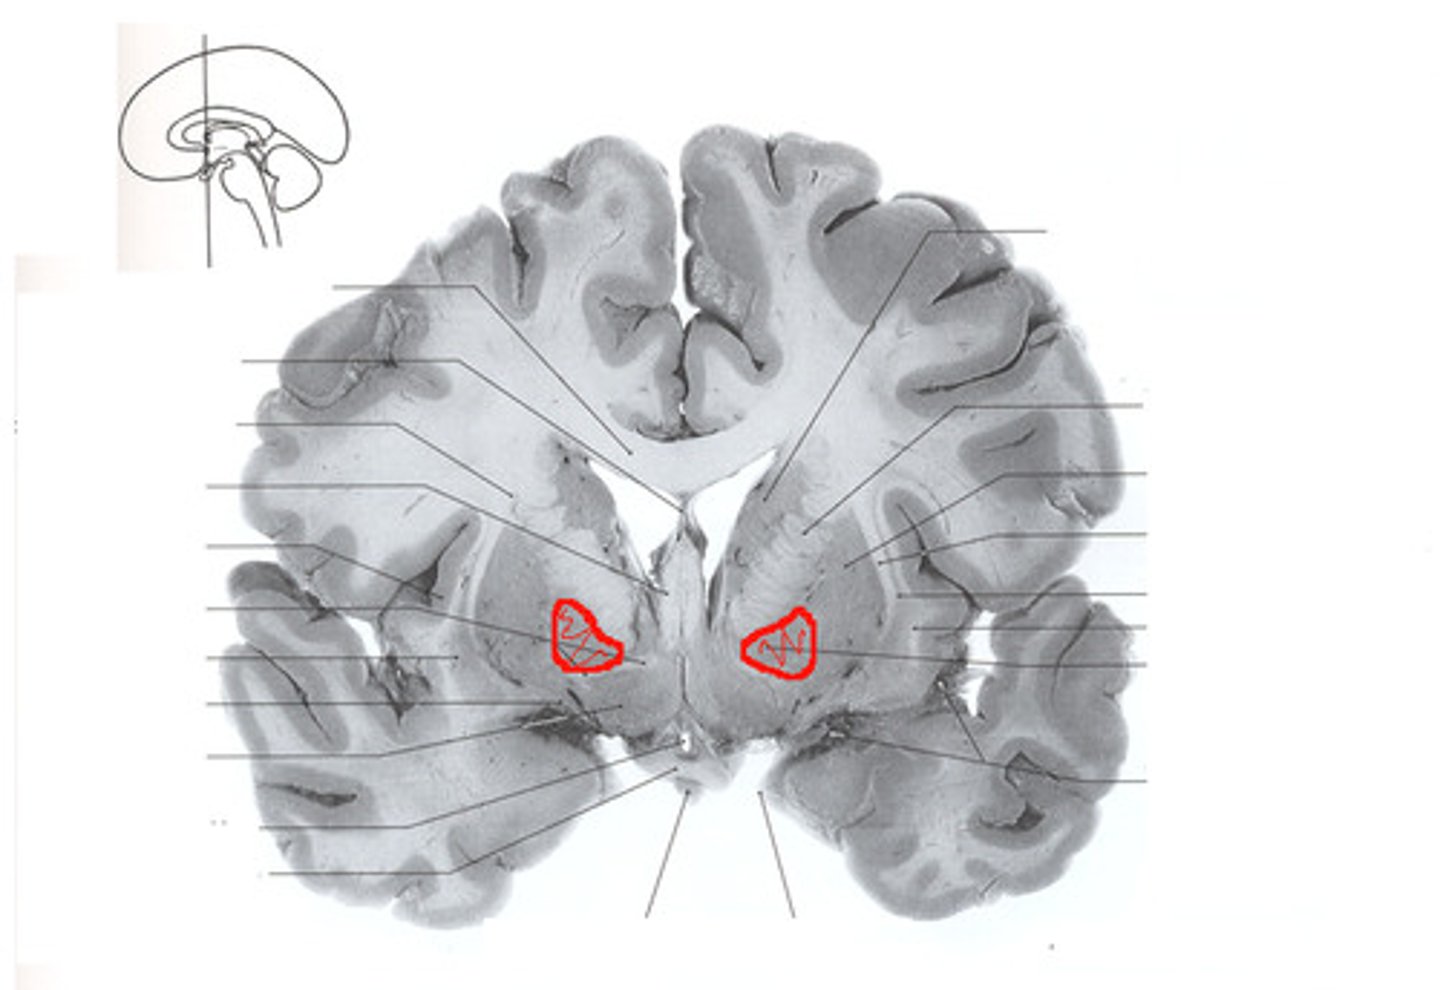

Caudate Nucleus

Globus Pallidus

Putamen

Choroid Plexus